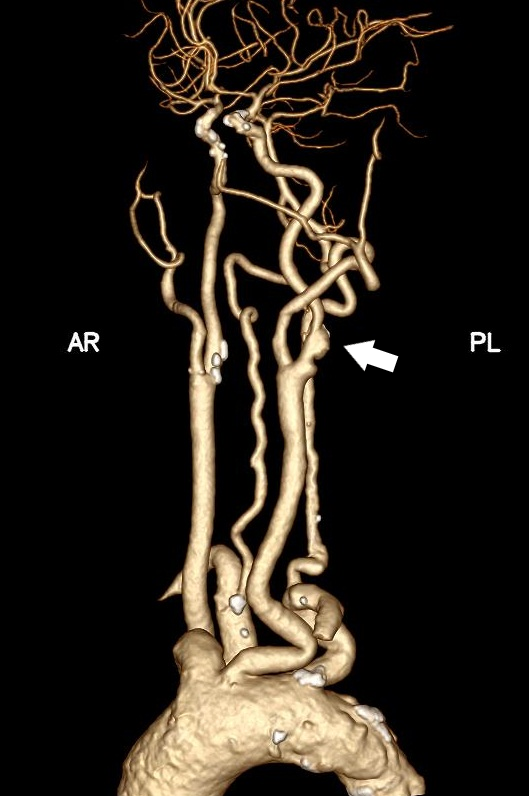

据悉,患者张某(化姓)因反复头晕就诊,检查后确诊为左侧颈内动脉重度狭窄,且主动脉弓为Ⅲ型弓,颈总动脉明显迂曲,且左侧颈动脉分叉位置较高,属于颈动脉狭窄治疗中较为复杂的解剖类型。若采用传统经股动脉颈动脉支架置入术,导管通过主动脉弓及扭曲血管难度大,脑栓塞风险高;若行颈动脉内膜剥脱术,则会因为分叉位置高、术野暴露困难,手术创伤和技术难度也明显增加。

针对患者复杂病情,烟台毓璜顶医院血管外科团队在车海杰主任的带领下,开展了多轮术前讨论。在与患者及家属充分沟通后,最终确定采用国际前沿的TCAR技术实施治疗。手术当天,团队通过颈部小切口精准暴露颈总动脉,快速建立反转脑血流保护系统,在全程有效脑保护下完成病变段支架精准植入。术中造影显示,患者狭窄的颈内动脉恢复通畅,支架位置贴合理想,脑部供血得到显著改善。术后患者恢复顺利,无任何新发神经系统并发症,头晕等不适症状明显缓解,目前已顺利康复。

手术前后

宋富波表示,TCAR是近年来国际上治疗颈动脉狭窄的创新微创技术,融合了开放手术与腔内介入的双重优势。与传统术式相比,该技术通过建立反转血流脑保护系统,能有效减少操作过程中栓子进入脑循环的风险,同时具备切口小、创伤轻、恢复快等特点,尤其适用于高龄、合并多种基础疾病或解剖条件复杂的高危颈动脉狭窄患者,从源头上提升了手术的安全性和有效性。